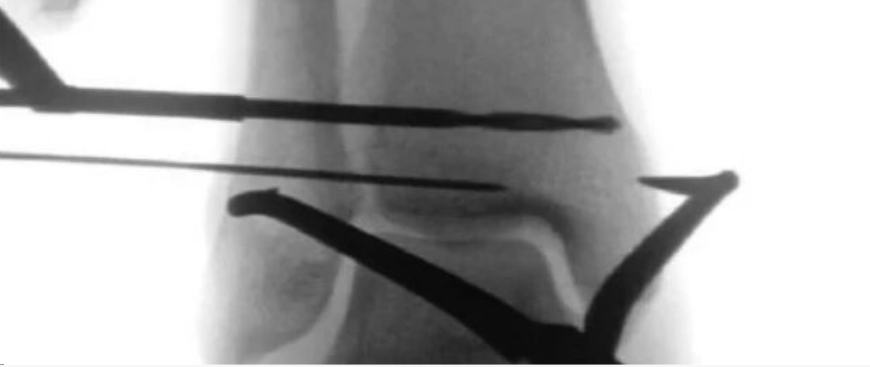

腓骨髓内钉固定减少一个切口可行吗?